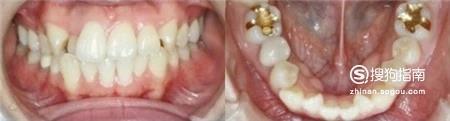

矫正之前,可以看出,虎牙很明显,参差不齐,上下牙齿排列也不整齐。

最后效果还是很理想的,变化真的很大呢!